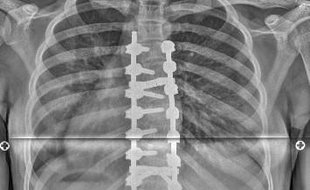

Náš tým operatérů z oddělení chirurgie páteře dostal v minulých dnech příležitost vyzkoušet v praxi nový páteřní systém, který splňuje nejpokrokovější požadavky korekce páteře a nabízí dosud nejmodernější způsob řešení dětské skoliózy. Naši lékaři operovali pomocí tohoto systému dvě dívky ve věku 13 a 14 let. U obou se zcela zásadně podařilo nejen srovnat páteř, ale i vrátit zrotované obratle do správného postavení, a odstranit tak nechtěné kosmetické deformity.

Systém Ennovate, na jehož vývoji se významně podílel přednosta Ortopedické kliniky Fakultní nemocnice Brno prof. MUDr. Martin Repko, zatím není na trhu chirurgických nástrojů volně dostupný. Jeho německý výrobce, společnost B. Braun, jej totiž ve spolupráci s odborníky z celého světa stále zdokonaluje a s žádostí o zpětnou vazbu se nyní obrátil také lékaře našeho oddělení chirurgie páteře.

Jsme rádi, že nám náš dlouholetý partner umožnil tento systém vyzkoušet a že ho zajímá náš názor. Tohle instrumentárium funguje na principu, který se využívá už řadu let, ale tento nový systém je sofistikovanější a efektivnější než jakýkoliv jiný, s kterým jsme kdy pracovali. Největší přínos vidím v tom, že spojení nástavců se šrouby zavedenými do páteře je hodně pevné a umožňuje takřka stoprocentní derotaci páteře.“

MUDr. David Buzek, primář oddělení chirurgie páteře KHN

Srovnáním a navrácením zrotované páteře do správné polohy dochází k odstranění kosmetické deformity. Tou je nejčastěji hrb nebo asymetrie prsou u dívek. Dalšími přednostmi uvedeného systému jsou podle karvinských lékařů snadnější manipulace a méně šroubování.

Nový systém, který by odpovídal nejmodernějším požadavkům na korekci deformit páteře, se v německém Tuttlingenu vyvíjí už několik let. Celosvětově první operaci dětské skoliózy pomocí systému Ennovate provedl  koncem roku 2020 v brněnské fakultní nemocnici profesor Repko, dále byl systém využit v jedné z německých nemocnic a ve třetím případě dorazil k nám do Karviné.